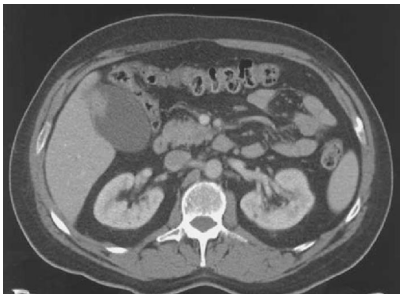

Mulher 57 anos. Assintomática do ponto digestivo. Realizou TC do abdome sem contraste para avaliação de cólica

nefrética e suspeita de ureterolitíiase.

Após avaliação da imagem abaixo, você indicaria qual procedimento cirúrgico?